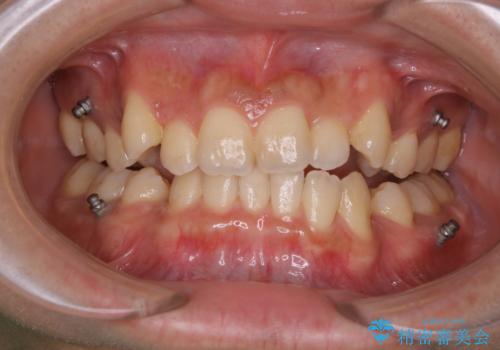

インビザライン単独でここまでできる!!抜歯矯正

- 治療計画

- マウスピースによる矯正治療をご希望された方です。歯のガタつきが大きかったため、ワイヤーによる抜歯矯正をご提案しました。どうしてもマウスピースが良いとの強いご希望があったため、治療の途中でワイヤー治療に切り替える可能性もあることを十分ご理解いただいた上でインビザラインによる抜歯矯正治療を行いました。

1日20時間以上、正しくインビザラインを使用して頂いたおかげで、ワイヤーに切り替えることなく矯正治療を終了することが出来ました。周囲からも歯並びがすごく綺麗になったと言われたのことで大変ご満足いただけました。